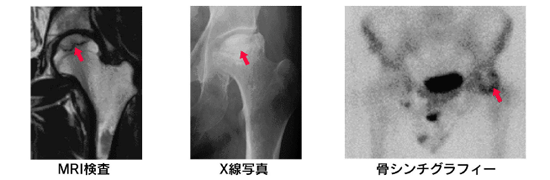

診断は早期には単純X線(レントゲン)で変化が見えませんので、疑われたらMRIを撮ります。

MRIで帯状低信号域などの特徴的な所見があれば確定します。他の部位の壊死も同時に診断したい場合には骨シンチグラフィーといって放射性同位元素を注射して全身骨格を撮影することもあります。